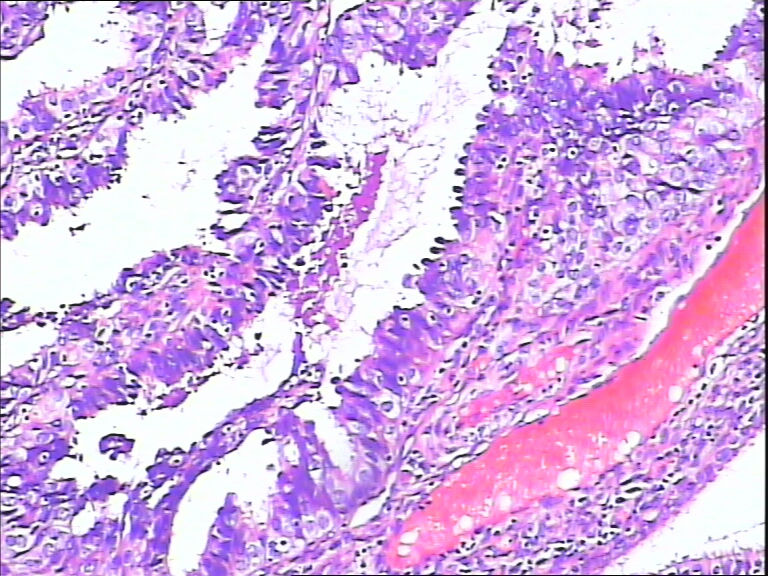

女,43y

左输卵管积液

输卵管长4.5cm;直径:0.8cm

• 请教:输卵管!图1

图1

输卵管增生性上皮病变。

慢性炎伴上皮增生

良性,炎症改变

考虑炎症